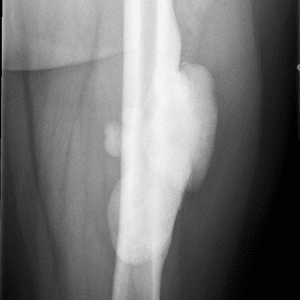

Pediatric Radiographs